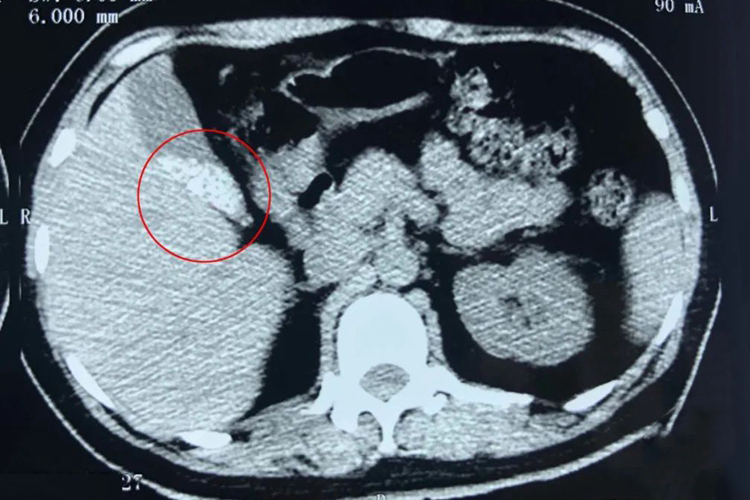

胆结石CT片子影像表现为高密度钙化影、高密度环影、等密度影、轻度钙化影和低密度影五种情况。胆结石中胆红素和钙含量高,其CT影像密度越高,CT值也越高。